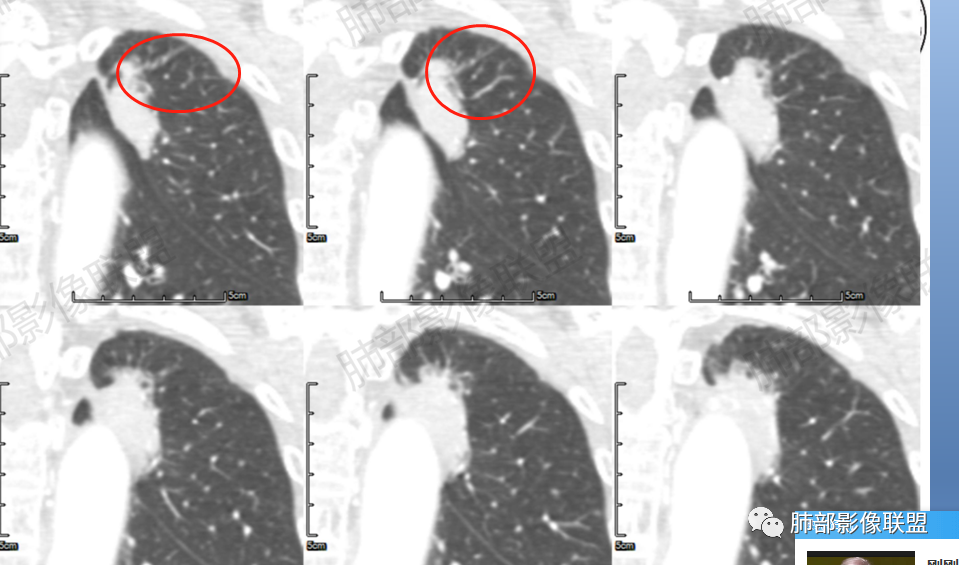

4.冠矢状位病灶于弓上部偏后局限性“贝雷帽”状突起,提示病灶有局部膨隆特点,且病灶上份及后份饰以边缘较清楚磨玻璃影。

3.如前所述本例病灶定位于尖后段肺组织,冠矢状位病灶明显局限性膨隆感,如有老师分析时称“见较清楚磨玻璃边缘”——这应当是本例较重要诊断线索!